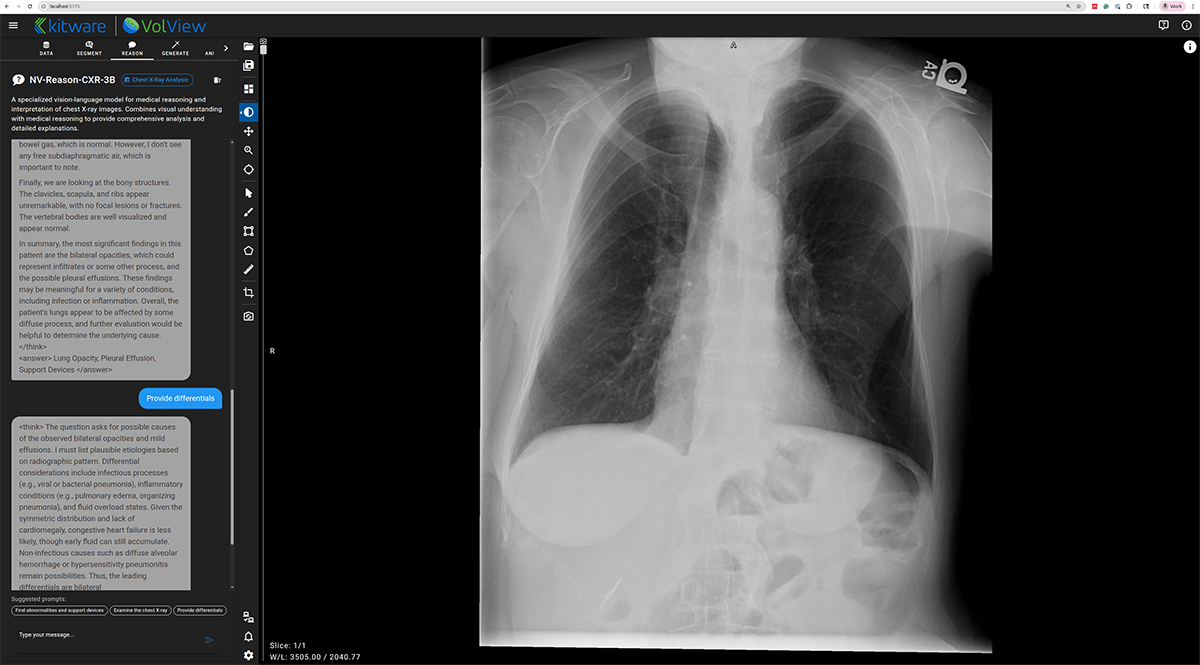

NV-Reason-CXR-3B — Clinically Aligned Chain-of-Thought Reasoning

NV-Reason powers an interactive, multimodal chat interface inside VolView, allowing users to ask questions directly about an image and receive structured, interpretable reasoning. This creates opportunities for explainability, teaching, quality assurance, and exploratory research.

During the demo, we show whole-body organ segmentation overlays, interactive correction, multimodal reasoning on chest X-rays, and the generation of high-fidelity synthetic CT volumes. The session concludes with deployment guidance and a Q&A session on customization, cloud scale-out, and governance.